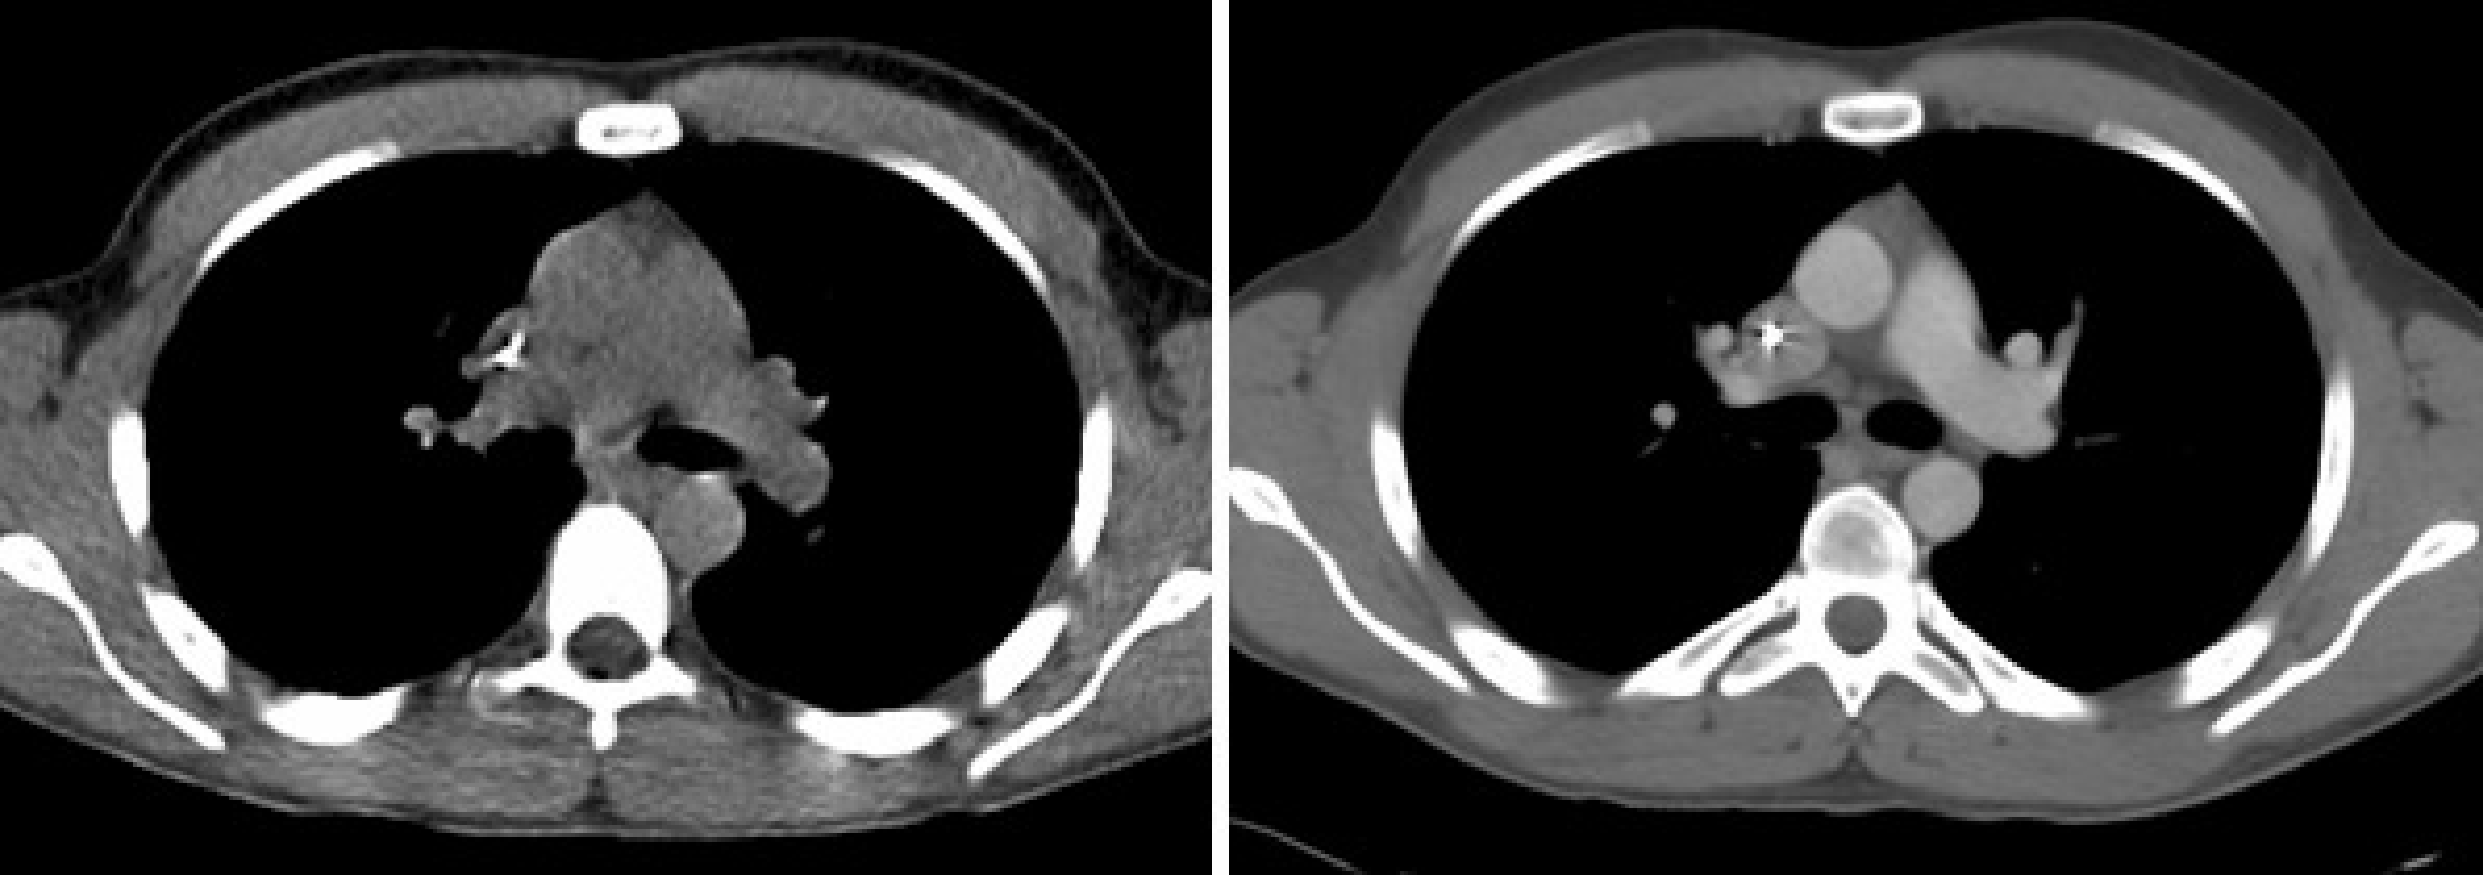

The time between the helical CT-scan and the last PET-scan is about half an hour. That is a long time to ly motionless, and in most PET/CT images one can see small positional mismatches due to patient motion. A similar mismatch is caused by breathing. The CT-scan is very fast compared to the breathing cycle, and essentially takes an image at one point of that cycle. In contrast, the PET-scan runs for a few minutes per bed position, and produces an image averaged over the breathing cycle. This causes motion blur in the PET image, and a registration mismatch with the corresponding CT image. The mismatch may yield attenuation correction artifacts in the PET image. An example of such an artifact is shown in Figure 12. The CT has been taken at maximum inhalation, causing the lungs in the CT-image to be larger than in the PET image. The patient increased his lung size mostly by a displacement of the diaphragm. The CT-based attenuation correction underestimates the attenuation at the dome of the liver (because the computer thinks this part has undergone lung attenuation, and the lungs are far less dense than the liver). This undercorrection, then, yields a decrease of apparent tracer uptake, making the activity in this part of the liver similar to that in the lung. As a result, the liver tumor seems to show up in the lung. The figure also shows an image obtained with attenuation correction based on a (well matched) transmission scan with a positron emitter, clearly showing that the tumor is in the liver.

Figure 12:PET/CT attenuation artifact due to breathing. The tumor is really located in the liver, but the mismatch with the CT and the resulting attenuation correction errors make it show up in the lung.This figure is from a paper by Sarikaya, Yeung, Erdi and Larson, Clinical Nuclear Medicine, 2003; 11: 943